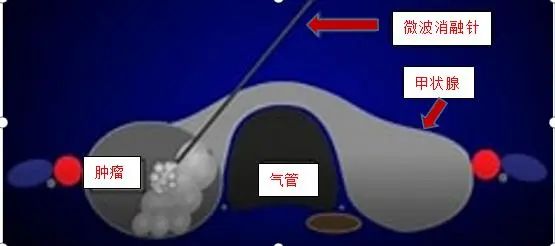

医师正在行微波消融治疗

据蒋汉城主任介绍,甲状腺微波消融手术就是经皮穿刺1.5mm消融针,直达甲状腺接电产生局部高温可以原位灭活大部分甲状腺组织,从而减少甲状腺素的释放,有望达到缓解或治愈甲亢的目的,同时该手术创伤小,恢复快,术后颈部完全不留任何疤痕,短期可以恢复正常工作。该微创手术的开展,实现了我院甲状腺外科手术由“刀”到“针”的微创转变。

微波消融术原理就是借助超声影像引导下将一根直径1.5mm左右的微波消融针穿刺刺入甲状腺病灶内,通过接电产生局部高温从而将肿瘤(结节)原位灭活,最后通过机体自身逐渐吸收而达到病灶缩小或消失。一般情况下术后1年病灶缩小可达85%以上,甚至完全消失,最终达到治疗目的。